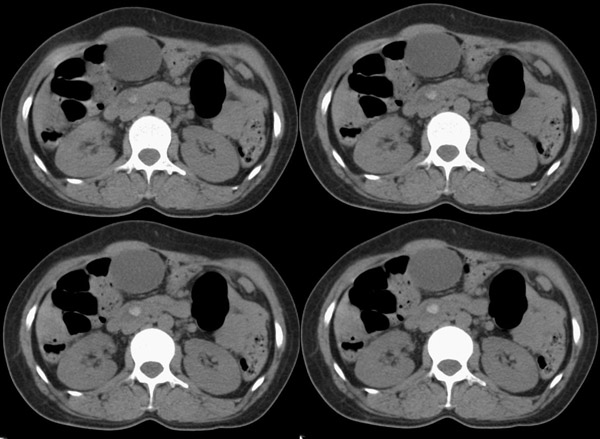

腹部ct平扫:(5mm层厚)

f42y近半月来无明显诱因出现右上腹疼痛之主诉就诊。疼痛多于饭后半小时发作,为持续性隐疼,呈阵发性、刀割样、钻顶样疼痛加剧,且向右肩背部放射,伴恶心、出汗、呕吐,呕吐内容物为胃内容物,无呕血,时有返酸、呃逆、烧心感,无腹胀、腹泻及黑便。时有发冷、发热(但体温不高);呕吐后腹疼稍有缓解,在当地诊所按“胃炎”对症治疗10天,效果不佳。血常规为:白细胞:9、8*109,中性64%,血红蛋白为151g/l,血小板为167*107。 既往有胆道蛔虫病史30余年,曾有呕虫史,否认肝炎及肺结核、溃疡病史。无外伤、手术及药物过敏史,陕西丹凤县四坪镇人,未去过疫区。

整个胆道系统内可见多发蛔虫钙化改变,胆道扩张.

行胆囊切除术及胆总管探查术:探查见肝脏大小正常,肝缘稍钝,肝表面光整,胆囊大小12*3*3cm3,壁水肿增厚约0。5cm,张力稍高,胆囊与大网膜呈纤维粘连;胆总管宽约2cm,壁明显增厚,触摸胆总管,隐约可触及一条状物,于胆总管做一长约1、5cm的纵行切口,用取石钳在胆总管内取出一条长约16cm长黑色的长条状物,较脆易折断,宽约0、6cm,证实为蛔虫尸体。用探子往下探,未发现下端结石最后诊断:胆道蛔虫症继发胆系梗阻性扩张。